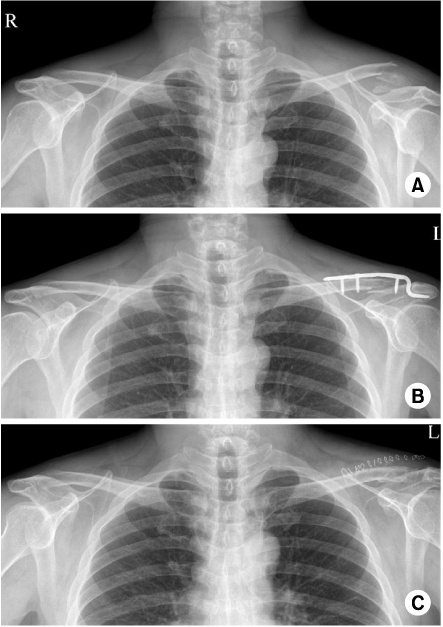

Fig. 2

(A) Preoperative radiograph of the left shoulder of a 80 year old female shows distal clavicle fracture.

(B) This is postoperative radiograph with Hook plate fixation.

(C) At 1 months follow-up, radiograph shows clavicle shaft fracture.

(D) At 6 months follow-up, the union of fracture site was found.

Fig. 2 (A) Preoperative radiograph of the left shoulder of a 80 year old female shows distal clavicle fracture. (B) This is postoperative radiograph with Hook plate fixation. (C) At 1 months follow-up, radiograph shows clavicle shaft fracture. (D) At 6 months follow-up, the union of fracture site was found.